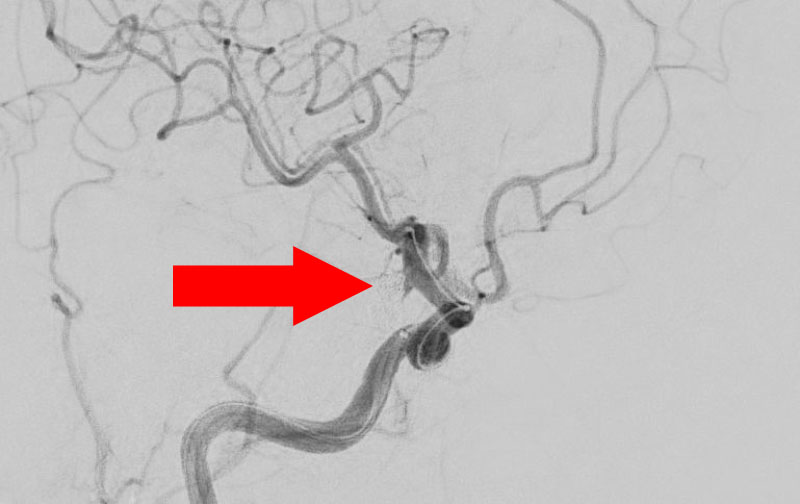

No.1602 手術中